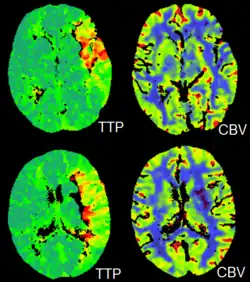

CT perfusion imaging is a specific form of CT to assess flow through blood vessels whilst injecting a contrast agent.[78] Blood flow, blood transit time, and organ blood volume, can all be calculated with reasonable sensitivity and specificity.[78] This type of CT may be used on the heart, although sensitivity and specificity for detecting abnormalities are still lower than for other forms of CT.[79] This may also be used on the brain, where CT perfusion imaging can often detect poor brain perfusion well before it is detected using a conventional spiral CT scan.[78][80] This is better for stroke diagnosis than other CT types.[80]